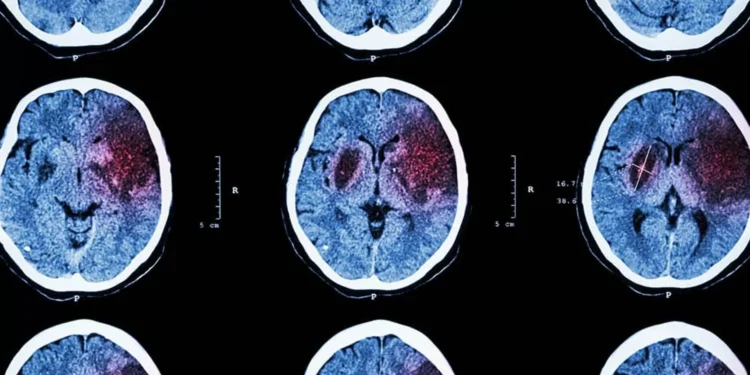

Os pesquisadores utilizaram técnicas de neuroimagem para monitorar a atividade cerebral de voluntários enquanto eles realizavam tarefas que envolviam tomada de decisão. Eles descobriram que, além do córtex pré-frontal, outras regiões do cérebro, como o córtex parietal e o córtex cingulado anterior, também estavam ativas durante o processo de tomada de decisão.